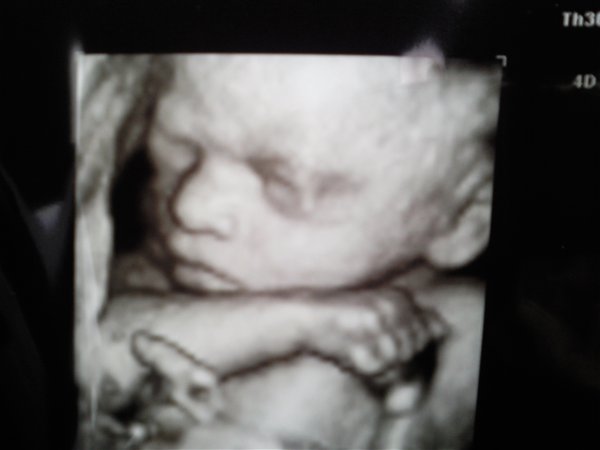

Her er Stellas nye Lillebror 27+3: